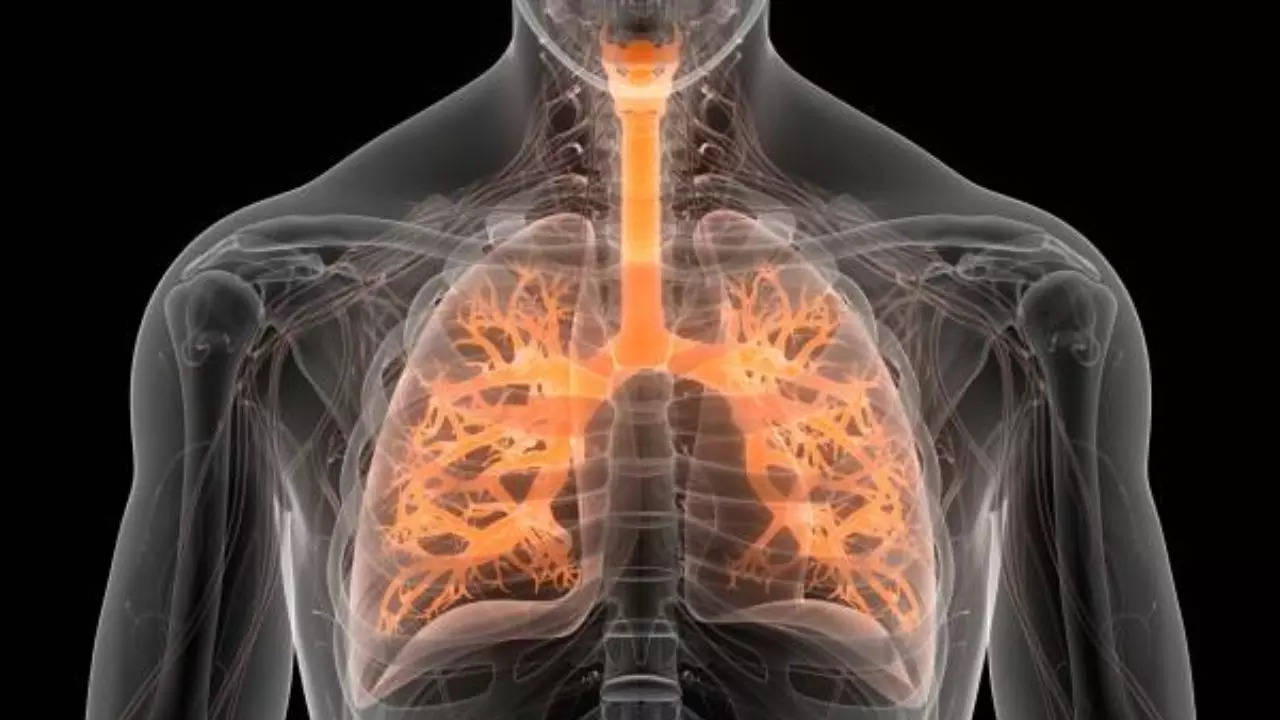

World Lung Day: हर साल की तरह इस साल भी 25 सितंबर यानी आज दुनियाभर में विश्व फेफड़ा दिवस मनाया जा रहा है। इस दिन को मनाने का उद्देश्य फेफड़ों के स्वास्थ्य के प्रति जागरूकता फैलाना है। फेफड़ो से जुड़ी बीमारी एक खतरनाक बीमारी है जिसकी चपेट में आने से मौत तक हो सकती है। फेफड़ों से जुड़ी बीमारियों का खतरा देशभर में तेजी से बढ़ता जा रहा है। फेफड़ों की स्थिति जैसे कैंसर, क्रॉनिक ऑब्सट्रक्टिव पल्मोनरी डिजीज (सीओपीडी, तपेदिक (टीबी), अस्थमा और एलर्जिक राइनाइटिस भारत में काफी बढ़ चुका है। इसके लिए जागरूकता फैलाने के लिए विश्व फेफड़ा दिवस मनाया जाता है। धूम्रपान, प्रदूषण, औद्योगिक गंद और अस्थमा इन बीमारियों के बढऩे में अहम भूमिका निभा रहा है।

फेफड़े, मानव शरीर के सबसे अहम अंगों में से एक मानें जाते हैं। इन दिनों फेफड़ों की बीमारी धूम्रपान, प्रदूषण, श्वसन संक्रमण आदि जैसे कई वजहों से बढ़ती जा रही है। श्वसन संबंधी स्थितियां सभी देशों में लोगों को प्रभावित कर सकती हैं। हालाँकि, यह निम्न और मध्यम आय वाले देशों (LMIC) को असमान रूप से प्रभावित करता है जहां प्रबंधन, रोकथाम और अनुसंधान के लिए संसाधनों की कमी है। हवा में रसायनों, कणों और संक्रामक जीवों के लगातार संपर्क में रहने के कारण फेफड़े बाहरी पर्यावरणीय कारकों से क्षति और संक्रमण के प्रति अत्यधिक संवेदनशील होते हैं। वैश्विक स्तर पर, कम से कम 200 करोड़ लोग बायोमास ईंधन के जहरीले धुएं के संपर्क में हैं, जो आमतौर पर इनडोर स्टोव (खराब हवादार) या फायरप्लेस में जलाया जाता है, 100 करोड़ लोग प्रदूषित बाहरी हवा और 100 करोड़ लोग तंबाकू के धुएं के संपर्क में आते हैं। विश्व फेफड़ा दिवस को मनाने का उद्देश्य लोगों को फेफड़ों के स्वास्थ्य के प्रति जागरूक करना है।